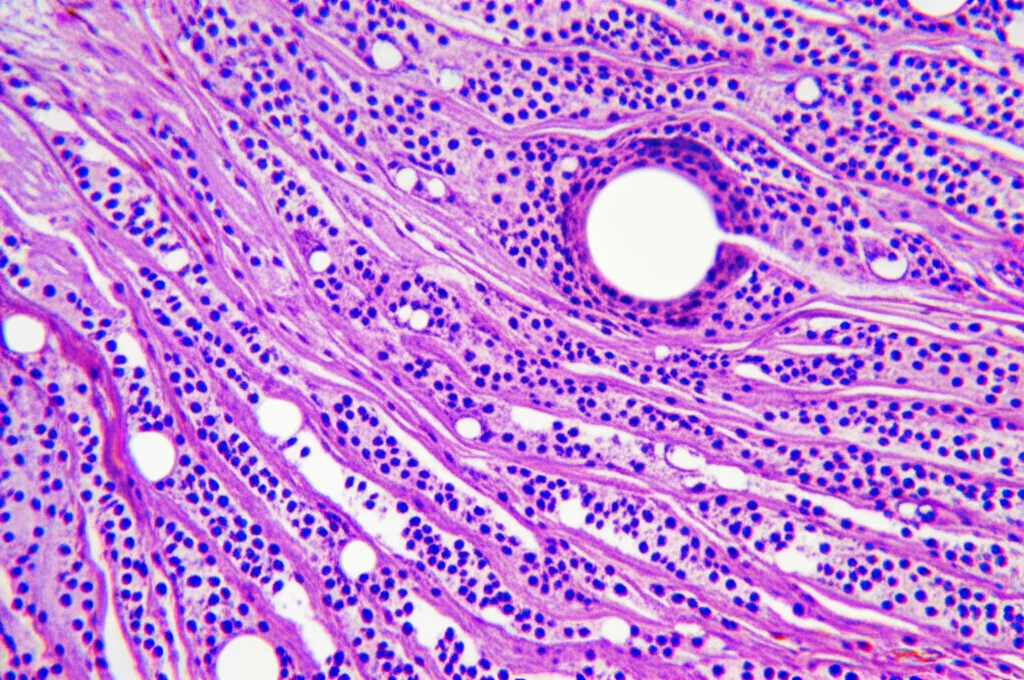

Per scoprirlo, abbiamo analizzato retrospettivamente campioni di tessuto tumorale e tessuto sano vicino al tumore (paratitumorale) prelevati da 199 pazienti operati per cancro al colon tra il 2006 e il 2012. Abbiamo usato una tecnica chiamata immunoistochimica (IHC), che ci permette di “colorare” la proteina PRMT5 nei tessuti e valutarne la quantità (o meglio, l’espressione).